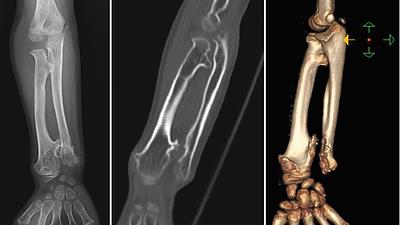

radiology.jpeg

Radiologia é fundamental no diagnóstico precoce de tumores ósseos pediátricos

26/08/2025, 13:20

O osteossarcoma é responsável por aproximadamente 60% dos tumores ósseos malignos em crianças e adolescentes, com a maior incidência entre 10 e 20 anos de idade.